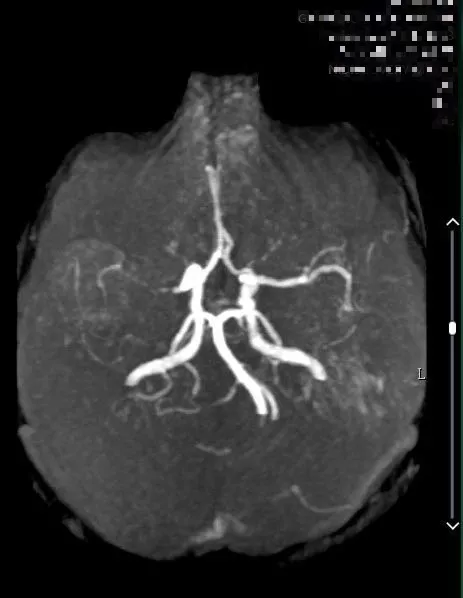

9:40分左右,患者逐渐开始出现烦躁、嗜睡,查体:言语不清,左侧肢体肌力0-1级,急查头颅MRI+MRA+颈部MRA阅片见,右侧基底节区急性脑梗死,右侧大脑中动脉闭塞。

头颅MRI+MRA(08-03日 11:50左右)

患者症状逐渐加重,头颅MRA示右侧大脑中动脉闭塞,是本次病灶责任血管,目前患者在取栓时间窗内,有行桥接动脉机械取栓指征。与患者家属沟通后全麻下行右侧大脑中动脉取栓术。手术风险及相关注意事项向患者家属告知。